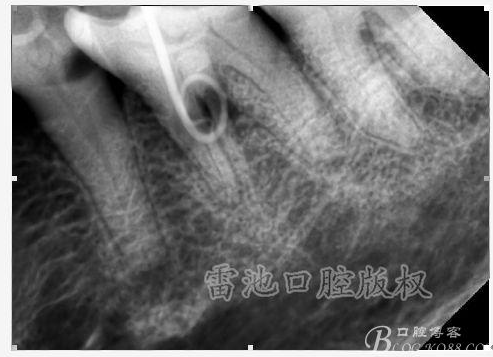

E 、X線影像學(xué)的檢查研判能力: 這點(diǎn)不需要強(qiáng)調(diào)太多,對于普通的非CBCT的二維影像對醫(yī)生讀片能力有一定的要求,有個(gè)逐步提高的過程,非一蹴而就,需要學(xué)會(huì)把二維的X線影像與三維的解剖結(jié)構(gòu)進(jìn)行良好的對應(yīng)結(jié)合,對于某些鈣化的髓室底,應(yīng)通過想象把根管口的分布、根管的走向以及各種變化通過想象投射到對應(yīng)的髓室底上;

G:找尋MB2的問題:

1、查閱各種文獻(xiàn),MB2的發(fā)生率在52-96%之間,治療時(shí)遺漏是上頜磨牙根管治療失敗的主因,2、一般位于MB1根管口與腭根管口方向的0.5-5mm范圍內(nèi),而大多數(shù)都位于MB舌側(cè)的1-3mm處,其中2mm以內(nèi)占85.7%,3、MB1-P根管口連線與MB1-MB2根管口的連線夾角大部分(74.3%)在30度以內(nèi);4、MB2的尋找大部分需要去除相應(yīng)部位的牙本質(zhì);5、當(dāng)找到的MB根管口呈“長線型”且有深色凹線向舌側(cè),或者找到的MB根管口明顯偏頰多提示有MB2的可能;6、DOM(牙科手術(shù)顯微鏡)的使用有助于找尋MB2;